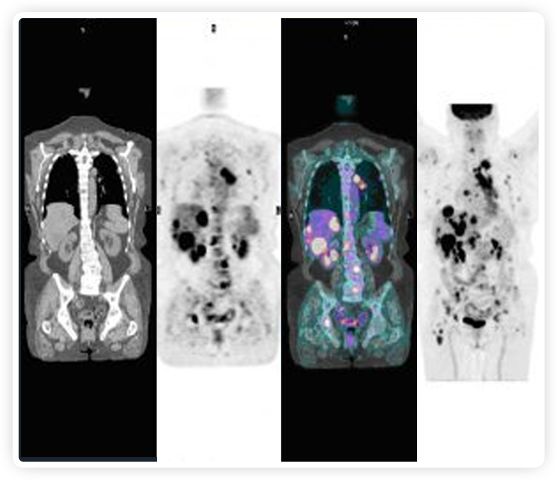

正電子發(fā)射斷層掃描(PET)是癌癥檢測(cè)中已建立的成像標(biāo)準(zhǔn),與其他成像方式相比,PET能提供高靈敏度和特異性的圖像。

到目前為止,放射腫瘤學(xué)中(使用的圖像主要是結(jié)構(gòu)性的,而PET圖像可以提供生物學(xué)信息。通過(guò)使用注射示蹤劑,例如18-FDG,PET可以描繪腫瘤的代謝活性,使其“點(diǎn)亮”。(FDG是用于可視化癌癥代謝的最廣泛使用的示蹤劑。與正常組織相比,腫瘤細(xì)胞保留更高水平的FDG。)不同的PET示蹤劑可以識(shí)別腫瘤的不同生物學(xué)特征,例如特定生物標(biāo)志物抗原(例如,PSMA)或甚至探測(cè)免疫系統(tǒng)本身(例如,PDL1表達(dá)或活化的T細(xì)胞)。